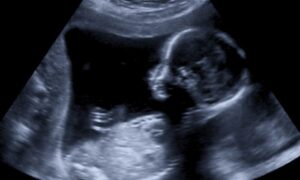

妊娠23週目にして二分脊椎を発見、そして手術へ

トゥリンクル夫妻(妻のジェシカと夫のスペンサー)の赤ちゃんのパーカーは、母親のお腹の中にいる時に二分脊椎という異常があると診断されました。2018年11月、定期健診でいつものように病院を訪れていた妊娠23週目のジェシカは、医者に別室に呼ばれ、パーカーの嚢が脊椎の中で大きくなってしまっているという説明を受けたのでした。